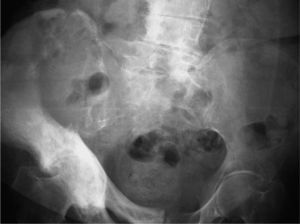

Mujer de 88 años diagnosticada de enfermedad de Paget en pala ilíaca derecha desde hacía un año sin necesidad de tratamiento. Acude a urgencias por dolor en la cadera derecha, de 3 meses de evolución, que empeora con el movimiento, la despierta por la noche y no cede con analgésicos habituales. La exploración sistémica y neurológica fue normal y en el aparato locomotor se objetivó dolor a la palpación y limitación a la movilización activa y pasiva de la cadera derecha en todos los planos, sin aumento de partes blandas. El estudio hematológico, bioquímico y de metabolismo óseo fue normal, con proteína C reactiva (PCR) y velocidad de sedimentación globular (VSG) normales y con fosfatasa alcalina (FA) de 130 (normal, 20-140) U/l. La radiografía simple de pelvis puso de manifiesto una lesión lítica de gran tamaño en el seno de un hueso pagético en pala ilíaca derecha con destrucción cortical y fracturas (fig. 1). Se realizó una tomografía computarizada (TC) de pelvis y caderas que confirmó la presencia de una lesión lítica con gran destrucción ósea, indicativa de osteosarcoma (fig. 2).

Radiológicamente, estas lesiones suelen ser líticas, junto a masa de partes blandas, destrucción cortical, espiculación ósea y/o fracturas sin signos de consolidación. Se acepta que un incremento en la VSG o la FA puede estar relacionado con la presencia de sarcoma. Nuestro caso tiene como peculiaridad la normalización de las pruebas biológicas, las que no nos ayudaron en el seguimiento de la paciente. Este hecho también se observa en la revisión de Cerdá et al4, donde se indica que no hay correlación entre los hallazgos biológicos y la malignización5.